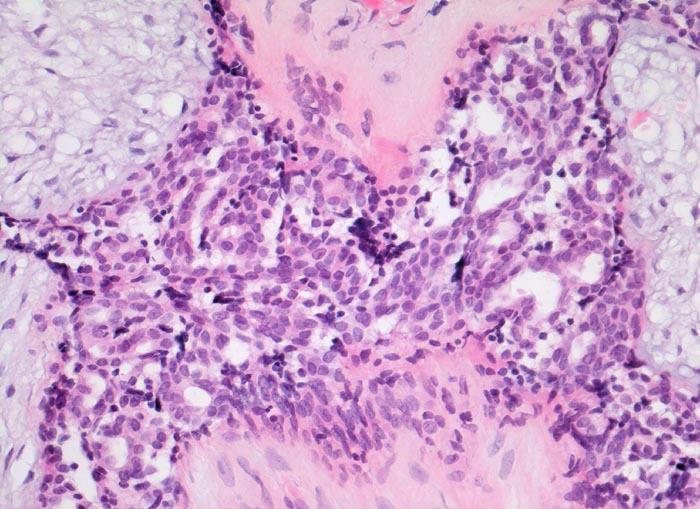

Das Stroma ist myxoid, fibrös-zellulär oder sklerotisch. Das zweireihige Epithel, welches die Spalten auskleidet, kann dieselben Veränderungen zeigen wie das normale Drüsenepithel (Epithelhyperplasie, Epithelmetaplasie, sklerosierende Adenose, Zystenbildung). In 0.2% aller Fibroadenome entwickelt sich ein in situ Karzinom (95%) oder ein invasives Karzinom (5%). Das juvenile Fibroadenom ist charakterisiert durch zellreiches Stroma, Epithelhyperplasie, rasches Wachstum und beträchtliche Grösse.